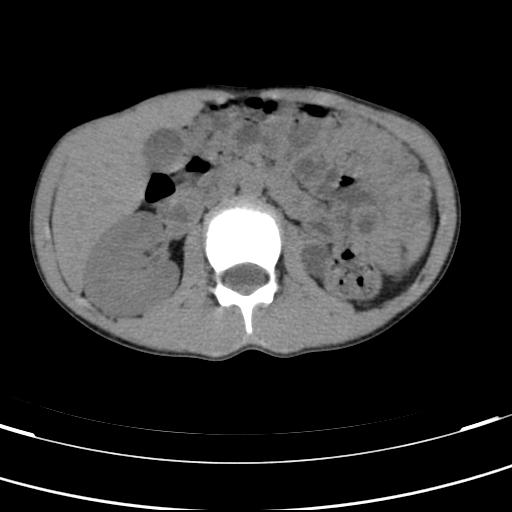

标题: PED3157:左肾缺如,请教脾脏的改变?、、

男孩,9岁。胃部不适。

左肾发育不良

脾脏变异,左肾未见,游走、异位、发育不全都要可能,增强或ivp造影。

脾脏位于左侧,但数个脾脏呈分离状态,左肾缺如,右肾代偿肥大。考虑多脾综合征。